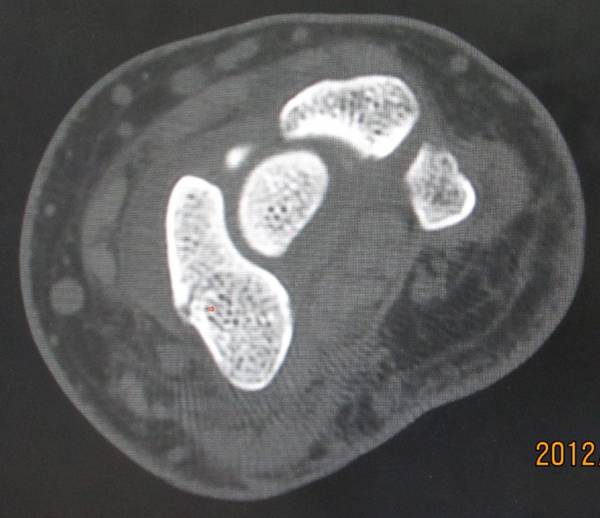

今天去ct室拍了一组舟骨骨图片

在机房看的动态的图像,想怎么看就怎么看

随便转

对骨质结构情况一目了然

太清楚了

舟骨骨折

一侧皮质断裂

平片不明显,幸亏做了CT